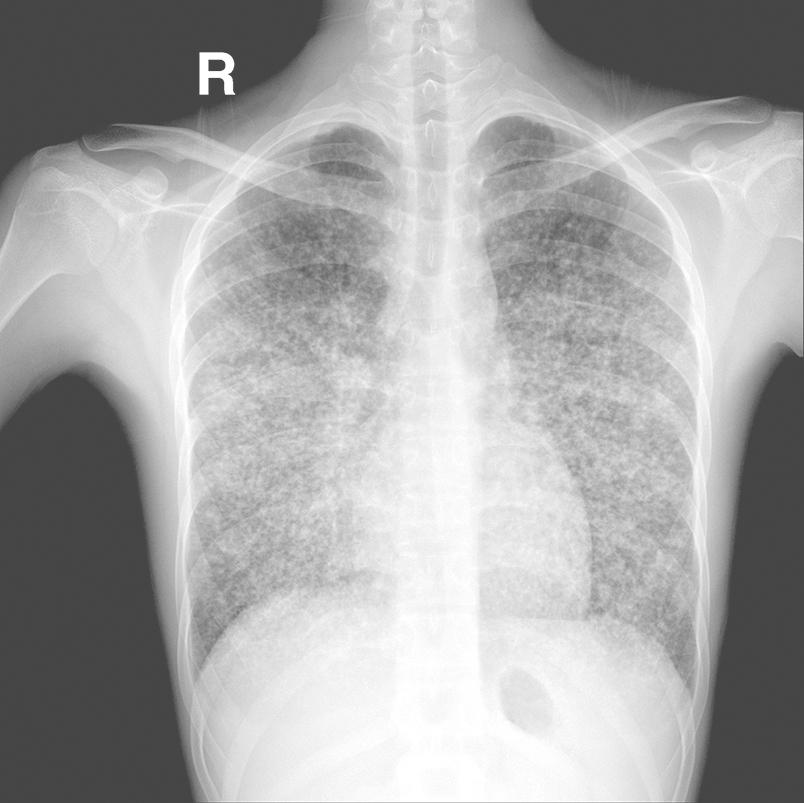

此型包括急性血行播散型结核(急性粟粒型肺结核)及亚急性、慢性血行播散型肺结核。原发型肺结核的早期菌血症可演进为血行播散型肺结核。此型也可由于肺或其他脏器继发活动性结核病灶侵蚀邻近淋巴管、血管而引起。血行播散型肺结核根据病程可分为急性、亚急性或慢性。前者为急性全身血行播散型结核病的一部分,起病急,持续高热,全身中毒症状严重,可伴发结核性脑膜炎。X线胸片显示双肺均匀分布大小一致(约2mm)的粟粒样结节影(图2-9-1)。早期病灶在X线胸片下常表现为肺纹理增多,易被忽视而漏诊或误诊,故当疑及本病时,应短期复查X线胸片。在人体免疫力较强的情况下,少量结核分枝杆菌分批经血行进入肺部时,则播散病灶大小不一、新旧不等,较对称地分布于两肺中上部,此为亚急性或慢性血行播散型肺结核。患者多无明显中毒症状,病情发展较缓慢,经X线胸片检查时才发现。

图2-9-1 血行播散型肺结核